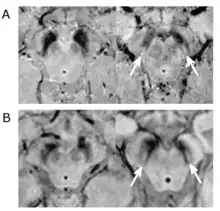

Le diagnostic de maladie de Parkinson est habituellement clinique. En théorie, la certitude du diagnostic n'est obtenue que par l'étude histologique du cerveau mais les critères diagnostiques actuellement définis permettent de faire le diagnostic sans trop de difficultés. Le scanner cérébral par tomodensitométrie des personnes atteintes de la maladie de Parkinson est habituellement normal[121]. L'imagerie par résonance magnétique sensible au fer (IRM T2*) peut être utilisée dans un cadre diagnostique. En effet, le fer peut être témoin de la mort cellulaire et le signal T2* diminue en présence de fer tandis que son inverse (R2*) augmente[122]. Dans la maladie de Parkinson, il existe une concentration en fer trop importante par rapport à la moyenne pour le même groupe d'âge au sein de la substance noire du fait de la perte de neurones dopaminergiques[123]. De plus, l'imagerie pondérée en fonction de la susceptibilité est elle aussi un marqueur fiable de la présence de fer intracérébral en étant à la fois sensible et spécifique à la maladie[124]. L'IRM T2* et l'imagerie pondérée en fonction de la susceptibilité sont toutes deux capables d'afficher le signe d'effacement de la queue d'hirondelle (swallow tail) dans la substance noire dorsolatérale. La tomodensitométrie et l'IRM sont également utilisées, en pratique clinique, pour écarter d'autres maladies pouvant engendrer un syndrome parkinsonien telles que l'encéphalite, les AVC chroniques, les tumeurs des ganglions de la base et l'hydrocéphalie[121].

Le Dat-scan est un type de scintigraphie cérébrale qui consiste à tracer les transporteurs de la dopamine de manière à pouvoir observer son parcours dans le cerveau. En effet, la tomographie par émission de positons (TEP) permet d'afficher l'activité métabolique des transporteurs dopaminergiques dans les ganglions de la base. Or, dans la maladie de Parkinson, on sait qu'il existe une mort pré-synaptique et les transporteurs de la dopamine disparaissent donc, le DaTSCAN est donc indiqué pour détecter la perte fonctionnelle des neurones dopaminergiques. Cette scintigraphie cérébrale (DaTSCAN) permettrait de montrer l'atteinte du striatum[125]. Un DaTSCAN est considéré comme normal si l'on peut observer une activité dopaminergique symétrique au sein des deux putamens des striatums, mais en cas d'asymétrie l'hypofixation dopaminergique est susceptible de dénoter une maladie de Parkinson. Le DaTSCAN corrèle bien avec le diagnostic clinique de la maladie de Parkinson[126]. De plus, une activité liée à la dopamine dans les ganglions de la base peut permettre d'exclure le syndrome parkinsonien iatrogène[121]. Une des premières indications du DaTSCAN fût de permettre la différenciation entre les tremblements essentiels des tremblements non essentiels (« parkinsoniens »)[127] et il dispose également également d'une AMM pour faire la distinction entre une démence due à la maladie d'Alzheimer ou une due à la démence à corps de Lewy. Toutefois, il faut noter que le DaTSCAN est incapble de différencier une démence associée à la maladie de Parkinson et une démence à corps de Lewy.